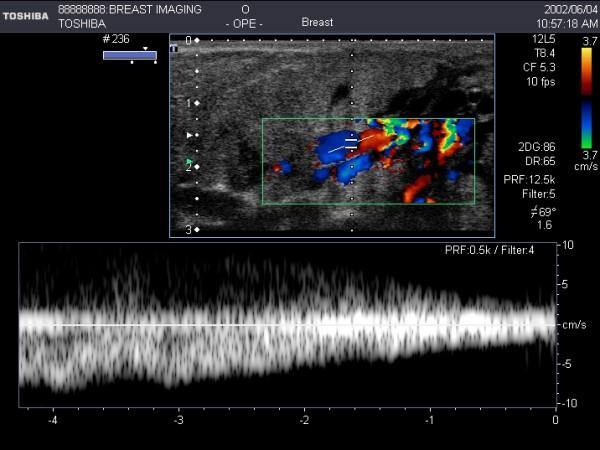

Diagnostic ultrasound imaging of the breast has been limited principally to the abnormal, non-lactating breast. Due to the rapid improvement of imaging technology, high-resolution ultrasound images can now be obtained of the lactating breast. Ultrasound scanning techniques, however, require modifications to accommodate the breast changes that occur in lactation. Furthermore, the function of the breast with regard to milk ejection can be assessed with ultrasound by identification of milk duct dilation and milk flow. At milk ejection, the echogenic duct walls expand as milk flows forward towards the nipple. Milk flow appears as echogenic foci rapidly moving within the milk duct. This paper provides a detailed description of the ultrasound technique used for the detection and reviews nuances associated with the procedure.

诊断性超声成像在乳腺方面的应用主要局限于异常的非哺乳期乳腺。由于成像技术的快速发展,现在可以获得高分辨率的哺乳期乳腺超声图像。然而,超声扫描技术需要进行修改,以适应哺乳期发生的乳房变化。此外,还可以通过识别乳腺导管扩张和乳汁流动来评估泌乳期乳房的功能。在泌乳期,随着乳汁向前流向乳头,高回声的导管壁扩张。乳汁流动表现为在乳腺导管内快速移动的高回声焦点。本文详细描述了用于检测的超声技术,并回顾了该过程的相关细微差别。